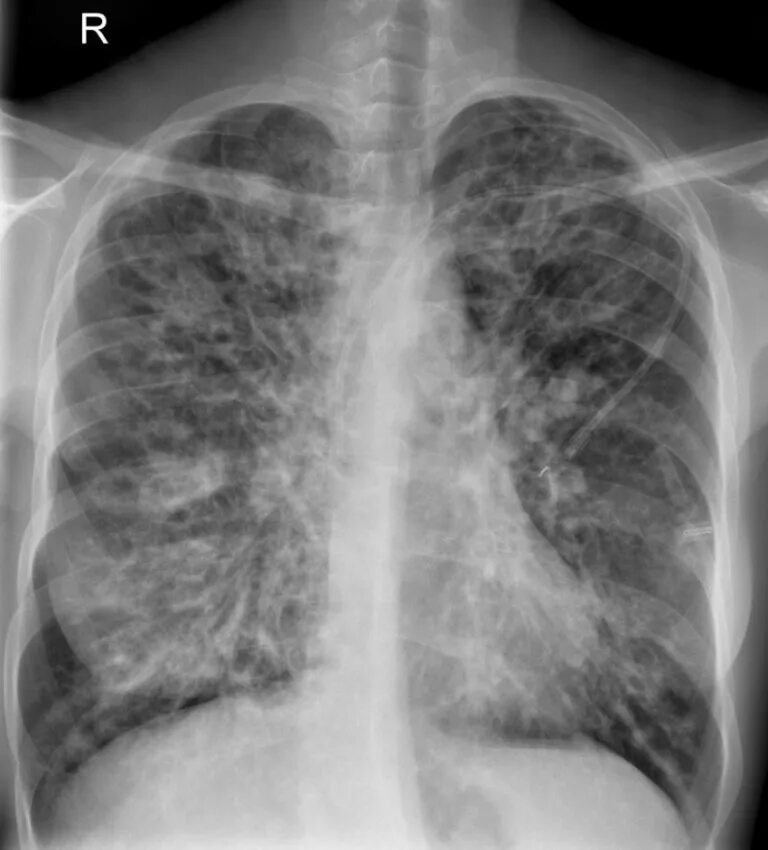

Фиброзное заболевание легких